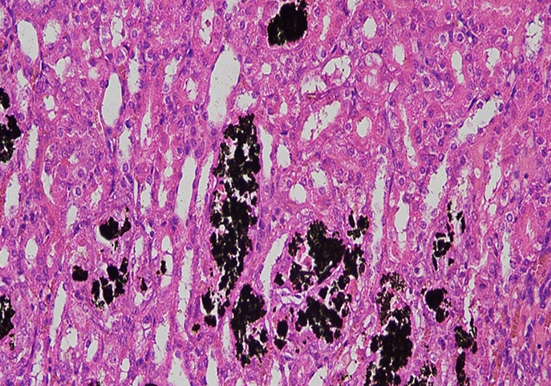

抗酸染色

以下是关于抗酸染色的详细介绍:基本原理细胞壁结构特殊:分枝杆菌的细胞壁含有大量的脂质,尤其是分枝菌酸,形成致密的蜡样包膜。这种包膜具有疏水性,普通染色剂的极性分···